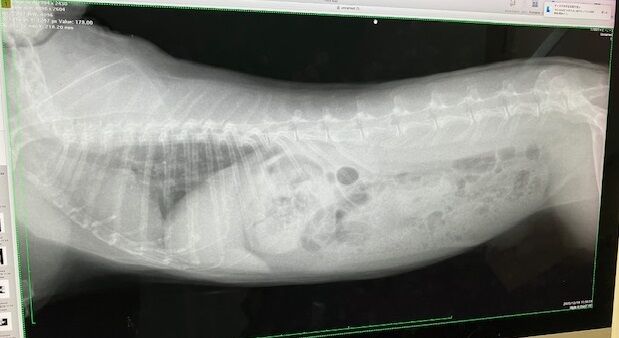

レントゲン

歯根への影響も見られず、共に良好でした